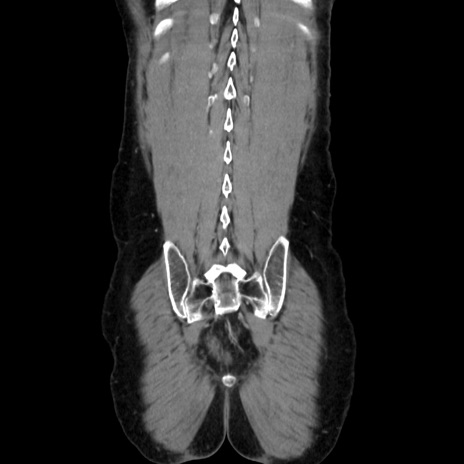

横断像